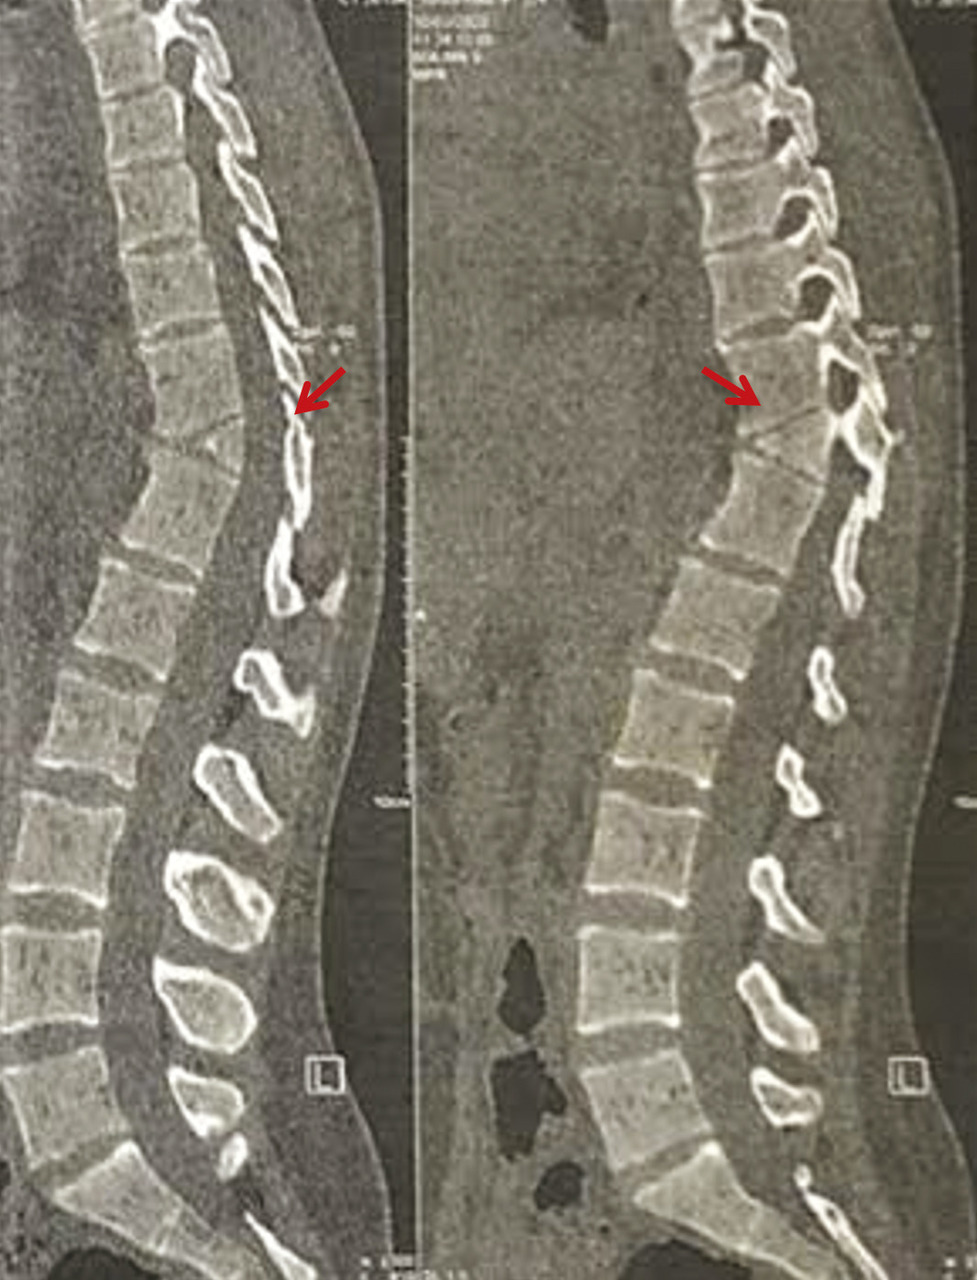

Une patiente de 25 ans, sans antécédents pathologiques particuliers, consulte pour des dorsolombalgies mécaniques avec une irradiation intercostale, sans déficit moteur ou sensitif. L’examen clinique met en évidence une hypercyphose dorsale et une hyperlordose lombaire. Les scanners dorsolombaires (fig. 1 et 2) objectivent une division complète du corps vertébral D11 en hémivertèbre dite « en aile de papillon ». La patiente est mise sous traitement symptomatique associé au renforcement des muscles paravertébraux et respiratoires avec une bonne évolution.

Il est important de comprendre les caractéristiques radiographiques des vertèbres papillon pour les distinguer des autres processus pathologiques (fracture, métastase, syringomyélie et maladie de Charcot). Un examen attentif des vertèbres adjacentes montre des caractéristiques de déformation de longue date, telles qu’un allongement exagéré des marges antérieures et un disque intervertébral normal. De plus, les vertèbres papillon causent généralement moins de cyphose. Plusieurs publications ont établi un lien entre les vertèbres papillon et les lombalgies1,9,10 dont le traitement est généralement conservateur. La cause de la lombalgie chez un patient avec des vertèbres papillon peut être sans rapport avec l’anomalie structurale et nécessite donc des recherches supplémentaires. Cependant, le traitement de la lombalgie dans la plupart des cas est généralement conservateur.